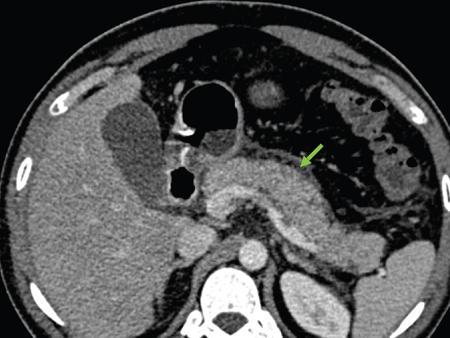

Anirudh Kohli Acute pancreatitis is one of the most dreaded diseases to afflict mankind, in view of its high morbidity and mortality. The single most important factor in reducing the morbidity and mortality of this condition over the last many years has been the role of computed tomography (CT). The incidence of acute pancreatitis is rising especially due to an increasing incidence of gallstones, obesity, as well as an ageing population. Pancreatitis occurs due to a chain of events triggered by a temporary/permanent pancreatic duct obstruction. This leads to activation and release of pancreatic enzymes into pancreatic interstitium and peripancreatic tissues leading to severe auto digestion and necrosis of pancreas and adjacent tissues. Systemically there is release of inflammatory mediators known as cytokines. Tumour necrosis factor is a cytokine which is toxic to acinar cells. These cytokines activate and intensify the inflammatory cascade that may ultimately culminate in multiorgan failure. Clinically severe acute pancreatitis is characterized by two phases, an early phase and a late phase. The early phase is dominated by the systemic effects of release of inflammatory mediators such as cytokines – termed as systemic inflammatory response syndrome (SIRS). Usually there is associated variable multiorgan dysfunction/failure. This phase lasts for a week. When the multiorgan failure lasts 2 days it is termed as mild, multiorgan failure lasting more than 48 hours is considered severe. There is no correlation between the clinical severity of pancreatitis and morphological changes in this early stage. In view of this CT scan is not of much utility during this phase, unless complications are suspected. The later phase is dominated by effects of local complications due to pancreatic/peripancreatic necrosis. Mortality follows this biphasic pattern in early weeks from the systemic effects of multiorgan failure and in later weeks due to local effects, for example infection of necrotic pancreatic/peripancreatic tissues superimposed by organ failure. The Clinical diagnosis of acute pancreatitis requires two of the following three features: If the first two findings are present without any significant SIRS then CT is not required. Acute pancreatitis is a complex disease with a wide variation in the presentation and outcome, ranging from asymptomatic with only biochemical alterations to a fatal outcome. In fact acute pancreatitis is a dynamic disease with continuously evolving appearances on imaging. There are two distinct forms of acute pancreatitis – interstitial oedematous pancreatitis and acute necrotising pancreatitis. Interstitial oedematous pancreatitis is a condition where there is only mild swelling of the pancreas with loss of normal lobulations and a diffuse decrease in attenuation of the pancreas. There may be heterogeneity of the pancreatic parenchyma due to varying degrees of interstitial oedema. This form of pancreatitis runs a mild course and rarely progresses to acute necrotising pancreatitis with its associated complications. In a third of these cases the pancreas may reveal no abnormality on a CT scan. The inflammatory changes may be restricted to the pancreas or extend into the peripancreatic regions. The inflammation in the peripancreatic regions manifests as acute pancreatic effusions. If there is peripancreatic fat necrosis with an oedematous pancreatic gland it is termed as acute necrotising pancreatitis (Figs. 9.17.1–9.17.2). Acute pancreatic fluid collections are enzyme-rich pancreatic juice collections seen in about 40% of patients with acute pancreatitis. The fluid collections occur due to exudation of pancreatic juices into the interstitium of the pancreas and subsequently leakage into the surrounding tissue spaces. These fluid collections are localized only by the anatomic space in which they collect. As the exudative process continues, the parietal peritoneum overlying the pancreas may be disrupted with the inflammatory fluid entering the lesser sac. From the lesser sac the fluid can enter the peritoneal cavity via the foramen of Winslow or by dissecting the peritoneum along the anterior surface of the lesser sac. Posterior extension of the fluid collection in the anterior pararenal space may occur into a potential space between the laminae of the posterior pararenal fascia. Rarely there may be involvement of the perirenal and posterior pararenal spaces. Other pathways of dissection are along the gastrohepatic, gastrosplenic and gastrocolic ligaments. Fluid may dissect along the root of the mesentery into the transverse mesocolon. Collections may extend around the caecum, ascending colon, descending colon and into the lumbar, pelvic and inguinal regions. Large fluid collections may dissect superiorly into the mediastinum or pericardial space. The quantity of fluid in these effusions is variable and can range from a small amount to large quantities (Fig. 9.17.3). Of these collections, 50% resolve spontaneously; the remainder may evolve after 4–6 weeks into pseudocysts. As the collections age, they tend to get localized and walled off, often developing an enhancing wall. A collection should be termed a pseudocyst only when a definite capsule develops and the collection has been static for at least 4–6 weeks. The risk of complications such as rupture, infection and haemorrhage increases with the age of the collection. Large collections of fluid are usually associated with a lesser degree of pancreatic necrosis as compared to extensive pancreatic necrosis associated with a lesser amount of fluid collection. Acute necrotising pancreatitis is a fulminant form of pancreatitis in which there is necrosis of the pancreas, that is nonviable pancreatic tissue. A contrast-enhanced CT is essential as it is the ideal means to demonstrate necrosis as well as to determine the extent of necrosis. These areas of nonviable pancreatic tissue do not enhance as compared to viable pancreatic tissue, which demonstrate significant enhancement. The extent of pancreatic necrosis has been found to correlate extremely well with the extent of necrosis found at surgery. The size, location and extent of pancreatic necrosis are very variable. These areas may be diffuse or focal, small in size to complete glandular involvement. These necrotic areas have a very important bearing on the course of pancreatitis, as they are liable to undergo secondary infection and form pancreatic sepsis. In addition, the more extensive the pancreatic necrosis the greater is the morbidity and mortality. Patients with no pancreatic necrosis have been found to have a 0% mortality and a 6% complication rate, whereas patients with pancreatic necrosis have a 23% mortality rate and an 82% complication rate. A variety of laboratory tests are available to detect pancreatic necrosis, such as a rise in the serum methemalbumin, quantitative estimation of C-reactive protein and urinary trypsinogen-activated peptide. CECT is still the most accurate modality to detect pancreatic necrosis. Pancreatic necrosis may be seen in the pancreas only, peripancreatic tissues also or only in the peripancreatic region. Isolated peripancreatic necrosis occurs due to disruption of the peripheral ductules with extravasation of activated pancreatic enzymes, may be seen in up to 20% of patients who require operative/interventional management of their necrotising pancreatitis. These patients with only peripancreatic necrosis have a better prognosis. This essentially represents retroperitoneal fatty tissue necrosis appearing as heterogeneous areas of liquid and nonliquid components. Over time necrosis evolves and liquefies as well as the liquid component resorbs. Generally if the liquid component is 2 cm or less it will resorb, while fluid collections 5 cm or more rarely resorb. If pancreatic necrosis is not resorbed it may get walled off or with time or may become infected. Encapsulation occurs between the third and fourth weeks. It is important to differentiate sterile from infected necrosis as sterile necrosis rarely needs surgery, whereas infected necrosis requires long-term antibiotic therapy and/or some kind of imaging/surgical intervention. According to the Atlanta 2012 classification, all areas of pancreatic necrosis are termed as acute necrotic collections. This represents a combination of pancreatic/peripancreatic fat necrosis with peripancreatic effusions. On CT, there is a spectrum of findings – solid, liquid containing debris (these may be nonwalled off/partially walled off). Sonography and MRI have advantages over CT scan in demonstration if the contents are pure liquid such as acute pancreatic effusions or have some nonliquefied components such as acute necrotic collections. Pseudocysts are round or oval encapsulated fluid collections containing only liquefied components. It takes 4 weeks for the granulation tissue to develop. On CT, a pseudocyst appears as a well-defined fluid collection with a thin capsule. The most common location for pseudocysts is the lesser sac, though they may be found anywhere in the mediastinum, abdomen or pelvis as they may dissect along fascial planes, along vessels and through capsules of solid organs. Pseudocysts in the bowel, though reported, are relatively rare, as the bowel wall is a strong barrier to the effect of proteolytic pancreatic enzymes. When the contents of the pseudocyst are heterogeneous or uniformly increased in attenuation, the possibilities of infection or haemorrhage should be considered. Focal areas of increased density within the fluid collection usually indicate haemorrhage. Complicated, enlarging or symptomatic pseudocysts require percutaneous catheter or surgical drainage. Infected pseudocysts are treated by percutaneous drainage. The management of a noninfected pseudocyst is controversial. Surgical treatment is only undertaken when the wall is mature after several weeks. Large pseudocysts greater than 5 cm in size can easily be drained percutaneously using intercostal drainage tube or pigtail catheter or endoscopically via the stomach. The cure rates are reported to be 85% with percutaneous drainage, the drainage period averaging about 20 days (Figs. 9.17.4–9.17.5). Walled off necrosis – as pancreatic/peripancreatic necrosis matures and evolves, an interface develops between necrosis and adjacent fatty tissue and an enhancing thickened wall is seen, resulting in a well-defined fluid collection with necrotic debris and fat necrosis. This is the end stage in the evolution of an acute necrotic collection. It is important to differentiate a pseudocyst from walled off necrosis, as a pseudocyst requires drainage and walled off necrosis requires surgical removal (Figs. 9.17.6–9.17.9). Sepsis is a major complication of pancreatitis and is accompanied by a high incidence of mortality and a prolonged hospital stay. Pancreatic sepsis may occur following secondary infection of pancreatic and/or peripancreatic necrosis, acute pancreatic fluid collections and pseudocysts. The only specific sign to demonstrate sepsis is the presence of gas in a collection. This occurs due to secondary infection by coliform/anaerobic organisms. This sign is unfortunately not common and seen in only one-third of cases. Gas is seen in the fluid collection as very dark well-defined air attenuation bubbles. Occasionally gas may be present due to a gastrointestinal fistula or previous surgery. Fat necrosis is seen in peripancreatic collections. This should not be confused with air bubbles, which are indicative of sepsis. The differentiation is easy to understand by CT, the values of fat ranging between – 20 HU and – 80 HU, and of air being >–300 HU. Also air bubbles have well-defined margins and are homogeneously jet black, whereas fat is nonhomogeneously grey with ill-defined margins. Since the presence of air is seen only in a small percentage of patients with pancreatic sepsis, the only other means to diagnose pancreatic sepsis is by CT-guided aspiration. All sites of fluid collection, parenchymal necrosis and peripancreatic necrosis are subjected to CT-guided aspiration. This is a tedious process and requires a dedicated interventional radiologist as there are often more than 5–6 sites from which it may be necessary to obtain samples. A fresh needle and syringe are used for each site, as it is important to know which site has sepsis and which is sterile. Care is taken not to transgress the large bowel as the colon has a large number of bacteria, and transgressing it could result in colonic bacteria contaminating the CT-guided aspiration sample, with falsepositive results. Further, colonic bacteria may be inoculated into a sterile acute pancreatic fluid collection or necrosis thereby converting a sterile collection into an infected one (Fig. 9.17.10). Complications of the procedure can be pneumothorax if the pleura is transgressed, haemorrhage due to trauma to a vessel, and secondary infection. Pancreatic sepsis is treated by surgical debridement, necrosectomy and drainage through thick tubes. It is crucial from the management point of view to differentiate an abscess from infected necrosis. An abscess may be treated by percutaneous drainage, whereas infected necrosis developing in relatively solid tissue can be treated by surgical debridement alone. Imaging-guided percutaneous drainage is the first step in treating pancreatic sepsis especially patients who are very ill and cannot undergo surgery. Initially pig tail catheters were used but these are notorious to get blocked as the largest bore of a pigtail catheter is 12 F. Pancreatic sepsis contains a large amount of necrotic debris, this blocks the catheters can be cleared by flushing the catheter, but this always raises the possibility of introducing secondary infection. To circumvent this issue large-bore ICD catheters have been introduced. These range from 16 F to 30 F. A safe window is necessary, not transgressing bowel or vasculature. It is quite easy to insert these tubes percutaneously under CT. A bit of initial manipulation and force is required to pierce the abdominal musculature. These large-bore drainage tubes have been very effective unless the infected necrosis is solid with minimal liquefied contents or a safe window for placing an ICD catheter is not available. CT is also invaluable in surgical planning and in the follow-up of postoperative patients to evaluate any fresh collection and also to determine whether the drains are well sited or not (Fig. 9.17.11).